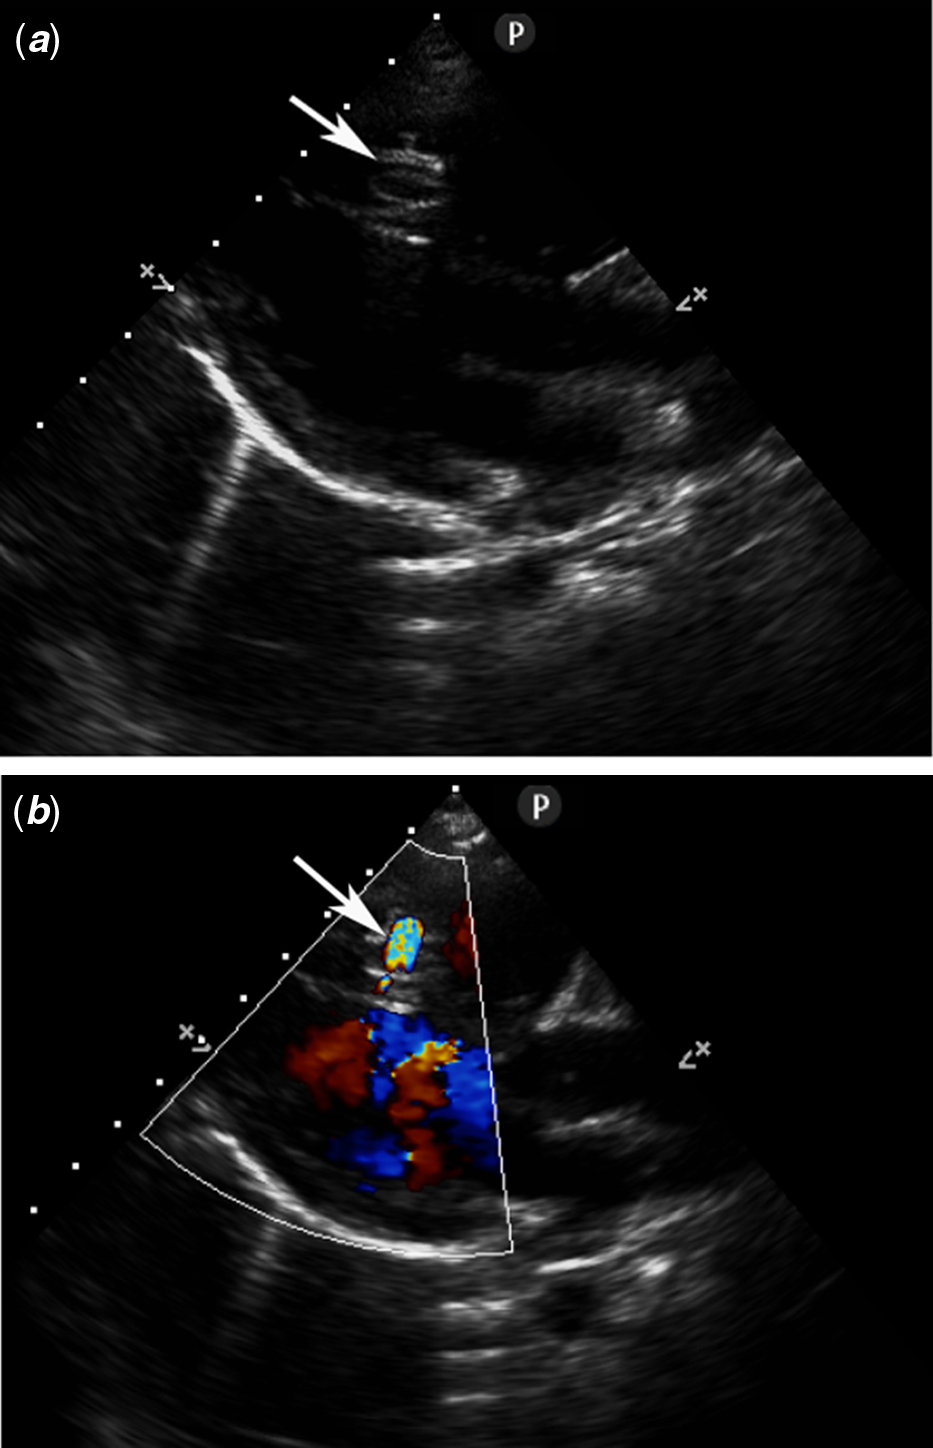

The procedures were performed under general anaesthesia with transthoracic echocardiography and fluoroscopic guidance. Heparin (100 U/kg) and prophylactic antibiotics (Cefazolin) were administered intravenously during the procedure. The maximum size of the defect was determined by either transthoracic echocardiography (Fig 2a and b) or left ventriculogram (Fig 3).

Figure 2. Parasternal long-axis view without (a) and with (b) colour Doppler demonstrating the MVSD (arrow). MVSD, muscular ventricular septal defect.